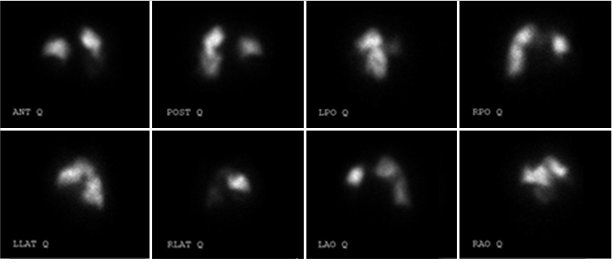

Cintilografia de V/Q (ventilação/perfusão)

Uma cintilografia de V/Q é recomendada e é o método de triagem do HPTEC preferido pelos especialistas. Esse exame pode detectar problemas nos pulmões que podem estar relacionados à HPTEC ou a outras condições.3,6

A cintilografia de V/Q é composta por dois testes — um exame de ventilação e um exame de perfusão. Durante o exame de ventilação, você inala um gás radioativo usando uma máscara, enquanto está deitado em um scanner.7

Durante o exame de perfusão, seu médico injeta uma solução especial na sua veia e coloca você em uma mesa móvel embaixo do scanner. O scanner permite que o seu médico veja se o sangue está fluindo pelos seus pulmões.7